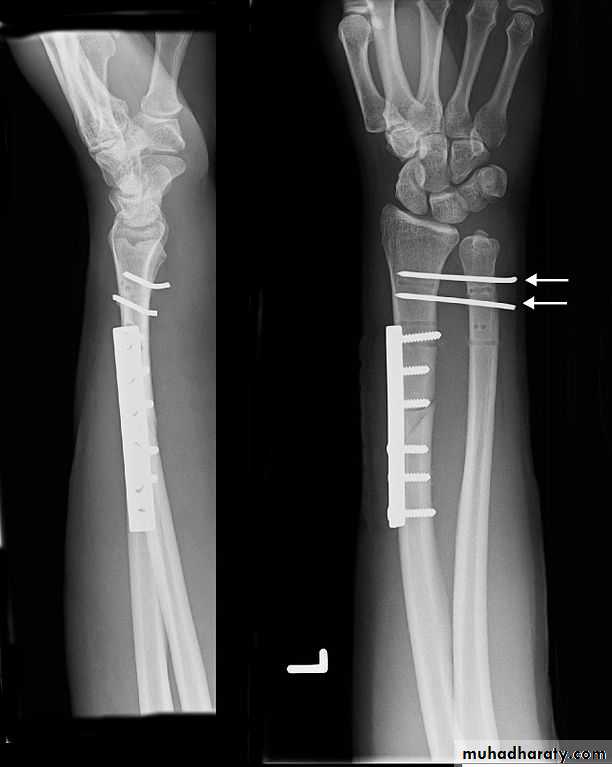

Upper limb

Fall on out stretched hand

xray

40 years male fall on out streched hand

Radial nerve palsy after reduction